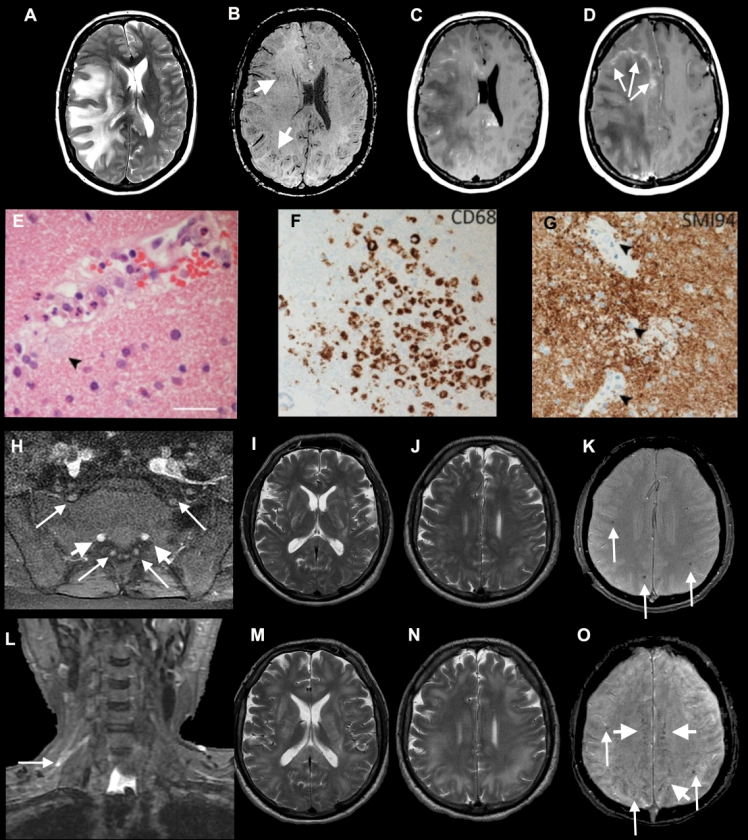

A growing body of research suggests COVID-19 can cause serious neurological problems.